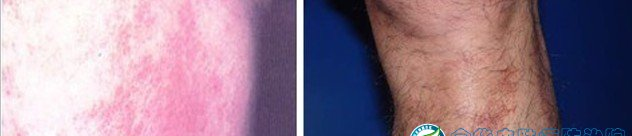

皮炎是一种常见皮肤病,表现为红斑,表面有针尖至米粒大小的丘疹、水疱、渗透液、结痂及脱屑,也可呈现苔藓样变,自觉瘙痒,日晒和遇热后会使症状加重等现象。医生建议,对于已经出现皮炎或者过敏症的人,应到正规医院诊治。下面是皮炎的图谱,如果你怀疑自己得了皮炎,可以对照下面谱图;

二、日光性皮炎